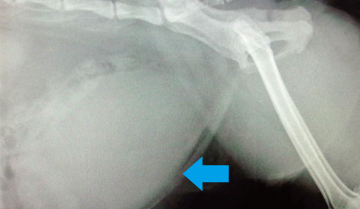

尿閉塞を繰り返したため会陰尿道造婁術を行った症例

昨日からおしっこがでないのを主訴に来院した雄猫です。

結石が尿道に詰まり排尿できなくなっていたため会陰尿道造婁術(新しく尿道を作る手術)を行いました。